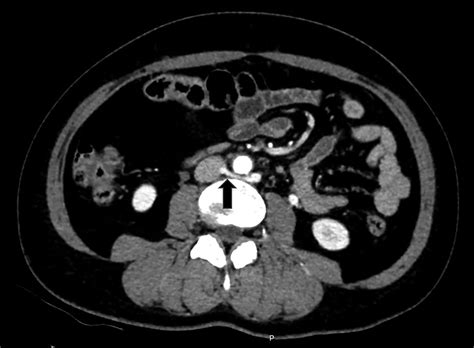

To grasp the mechanical nature of this condition, it is helpful to visualize the anatomy of the abdomen. The left renal vein travels horizontally across the abdomen to deliver blood from the left kidney into the inferior vena cava. In patients with Nutcracker Syndrome, the angle at which the superior mesenteric artery branches off the aorta is unusually narrow. This anatomical narrowing acts like a clamp, compressing the renal vein.

Diagnosing this condition requires advanced imaging techniques to visualize the vascular anatomy and confirm the compression. Doctors typically use a combination of non-invasive and invasive tests to determine the severity of the obstruction.

CT Angiography (CTA) Provides 3D images to measure the precise angle of the artery and the vein diameter.